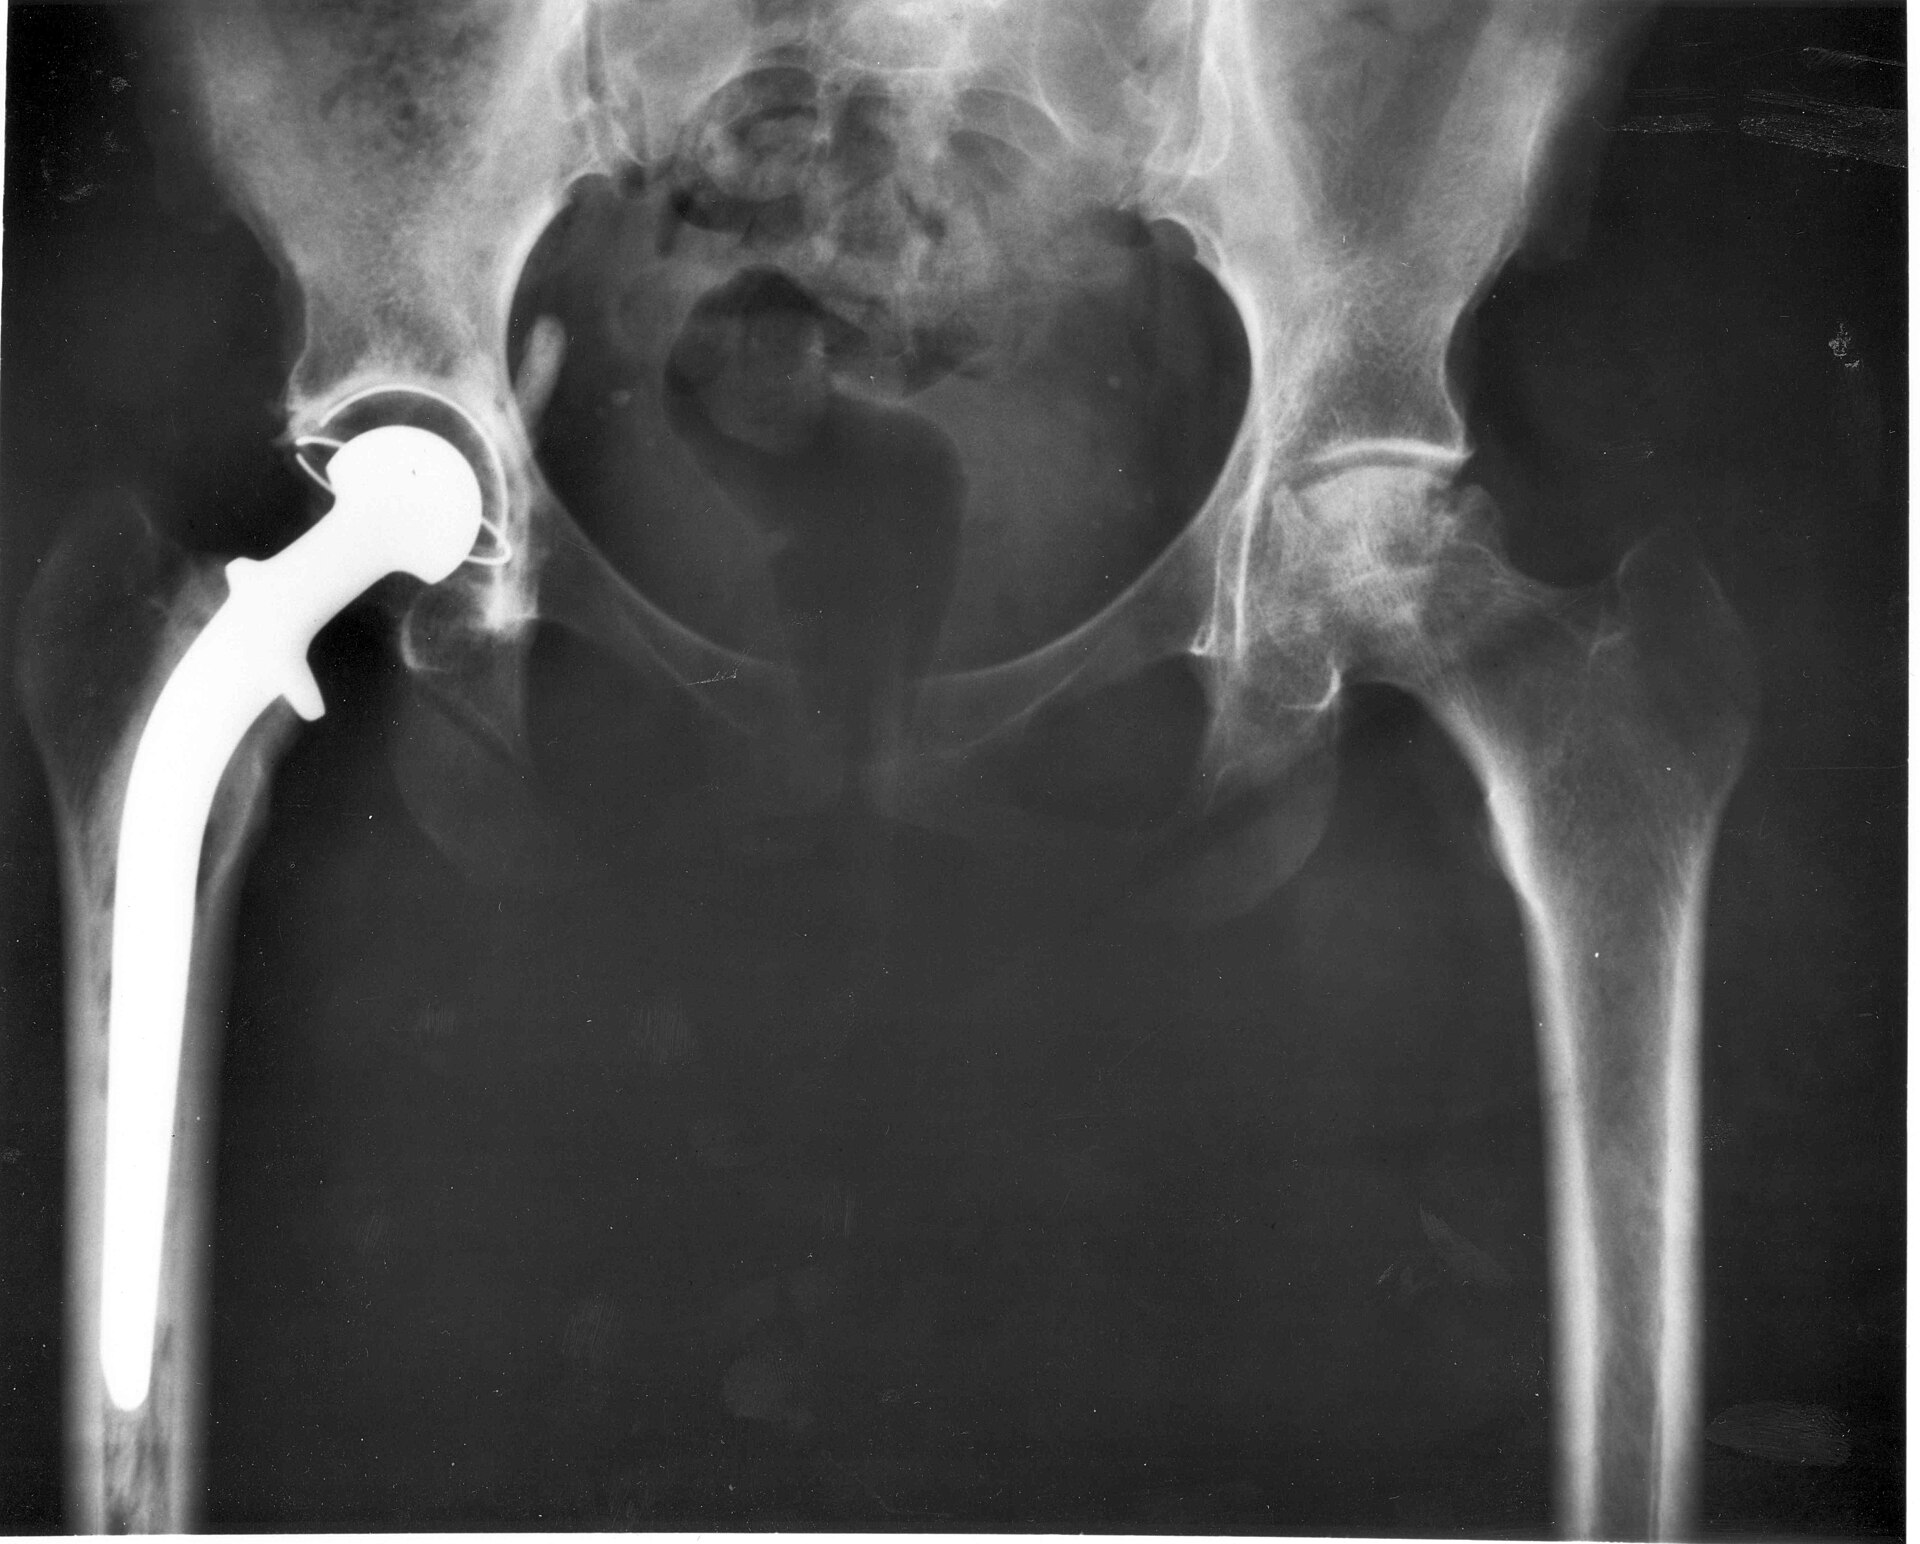

Radiograph of a total hip replacement showing the prosthetic femoral component.